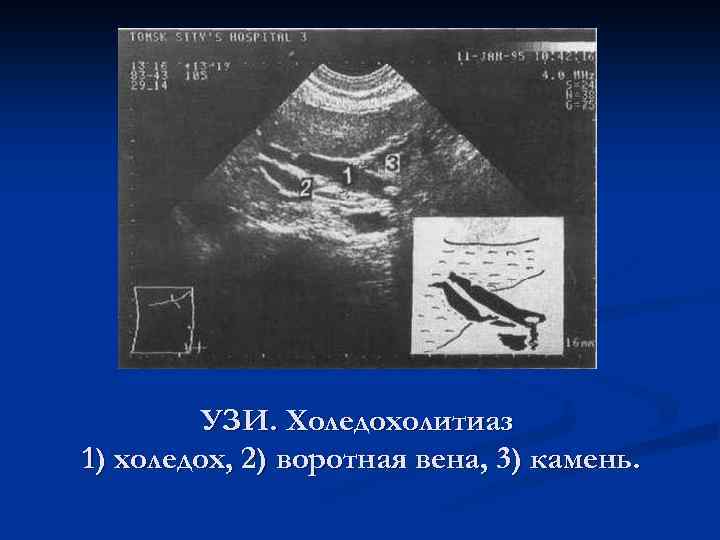

УЗИ. Холедохолитиаз 1) холедох, 2) воротная вена, 3) камень.

УЗИ. Холедохолитиаз 1) холедох, 2) воротная вена, 3) камень.

УЗИ. Холедохолитиаз 1) холедох, 2) воротная вена, 3) камень.

УЗИ. Холедохолитиаз 1) холедох, 2) воротная вена, 3) камень.